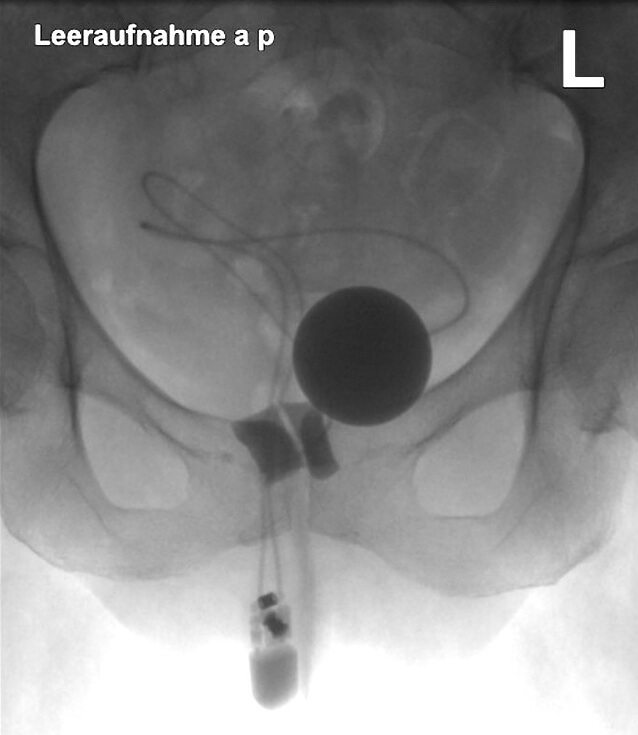

Bei 14 Frauen wurde ein artifizieller Sphinkter am Blasenhals implantiert. Nach einem medianen Follow-up von 95,9 Monaten waren 90,2 % kontinent; bei 5 Patientinnen wurden Revisionen notwendig (35,7 %). Ein Sphinkter musste wegen einer Harnröhrenarrosion explantiert werden (▶ Abb. 1 und 2) [5].